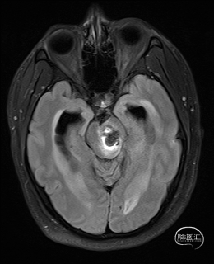

术前MRI检查

术前MRI检查提示左侧丘脑中脑海绵状血管瘤并卒中,梗阻性脑积水;

根据MRI及DTI显示,只有在丘脑与上丘之间的点(dot)进入病变才可能在切除病变时最大程度保护神经功能,由于上述原因,该“点”在术中显露极其困难,虽有导航指引,电生理监测的条件下,对术者的耐心、技术、经验及体能依然是极大的挑战;

选择经右侧幕下小脑上旁正中入路,应用神经内镜技术“一站式”切除病变,达到“一箭双雕”的目的,既切除海绵状血管瘤,又同时解除梗阻性脑积水,让患者最大程度获益。

术前详细的磁共振检查,包括平扫增强,SWI及DTI,可以规划出手术最适宜的路径及切入点;